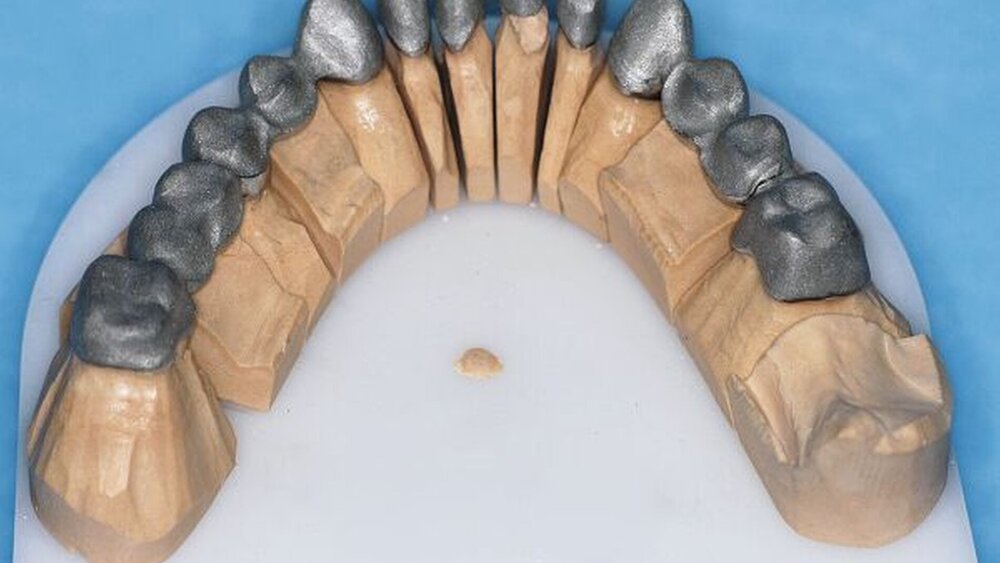

Die Abformungen des OK und des UK erfolgten als Korrekturabformung unter Verwendung eines A-Silikons. Zur Darstellung der subgingival liegenden Präparationsgrenzen wurden mit Adstringentien getränkte, geflochtene Retraktionsfäden in die Sulci aller Zähne eingelegt. Eine adäquate Trocknung der abzuformenden Bereiche wurde durch die Verwendung von Kompressions-Wattekappen, die auf den einzelnen Zähnen platziert wurden, durch Parotispflaster sowie durch eine konstante Absaugung erreicht. Um ein möglichst langes Verarbeitungsintervall zu erzielen, wurde das verwendete Silikon zuvor im Kühlschrank gelagert [Wöstmann et al., 1992; Wöstmann et al., 1999]. Nach erfolgter Abformung wurde ein Gesichtsbogen zur individuellen Übertragung des Oberkiefermodells in den Artikulator angelegt, danach wurden die Provisorien des I- und IV-Quadranten wieder befestigt. Nun wurden partielle interokklusale Registratschlüssel mithilfe eines intraoral anwendbaren Autopolymerisats im Bereich des II- und III-Quadranten angefertigt und beschliffen. In einem zweiten Schritt wurden die Provisorien im I- und IV-Quadranten entfernt und die partiellen interokklusalen Registratschlüssel des II- und III-Quadranten eingesetzt. In dieser Position wurden nun ebenfalls Registratschlüssel im I- und IV-Quadranten angefertigt und beschliffen. Durch dieses Vorgehen war es möglich, die im Rahmen der Registration ermittelte Position – unter Einbeziehung der präparierten Zahnhartsubstanz – auf die Modellsituation des Arbeitsmodells zu übertragen. Abschließend erfolgte die Farbauswahl. Die Arbeitsmodelle wurden mithilfe des zuvor angelegten Gesichtsbogens und der erstellten Registratschlüssel in einen teiljustierbaren Artikulator übertragen. Im Labor erfolgte die Herstellung der Nichtedelmetall-Gerüste der Einzelkronen 22, 32, 31, 41 und 42, die der Brücken 12 bis 21, 35 bis 37 und 43 bis 46 sowie die der Nichtedelmetall- Primärkronen 13, 14, 23 und 24.

In einer weiteren Sitzung erfolgten die Gerüstanproben der angefertigten Restaurationen. Alle Provisorien im Ober- und im Unterkiefer wurden entfernt und die präparierte Zahnhartsubstanz versäubert. Danach wurde die Passgenauigkeit der hergestellten Gerüste am Patienten überprüft. Dies erfolgte unter Verwendung einer Häckchensonde sowie eines niedrigviskösen Silikons. Zudem wurden die mechanische Stabilität, die Friktion und die technische Gestaltung überprüft.